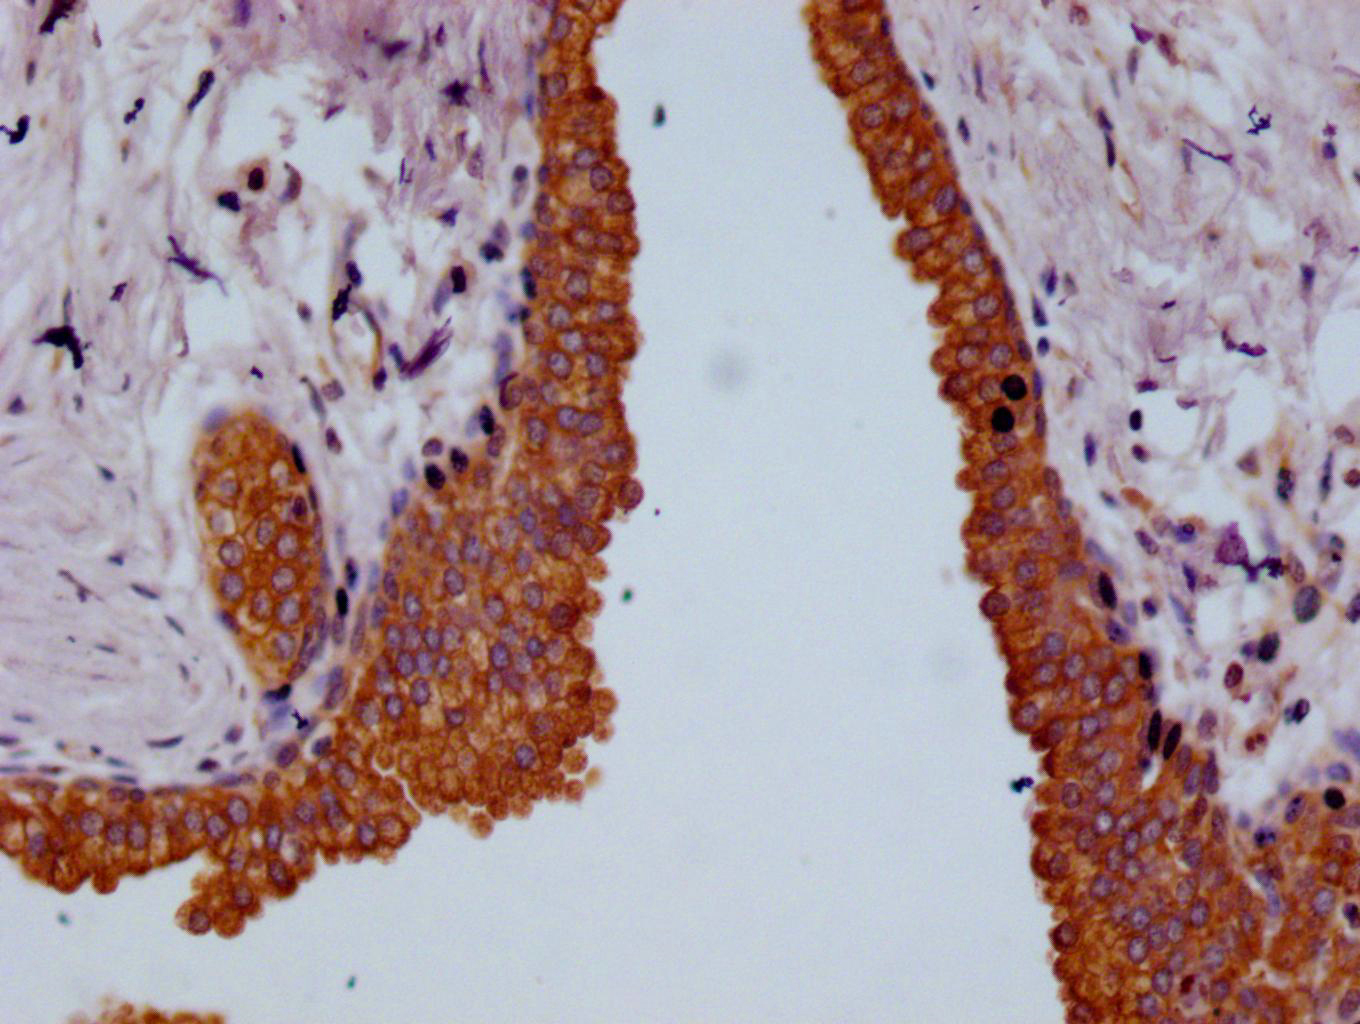

IHC image of CSB-RA959139A0HU diluted at 1:100 and staining in paraffin-embedded human colon cancer performed on a Leica BondTM system. After dewaxing and hydration, antigen retrieval was mediated by high pressure in a citrate buffer (pH 6.0). Section was blocked with 10% normal goat serum 30min at RT. Then primary antibody (1% BSA) was incubated at 4°C overnight. The primary is detected by a Goat anti-rabbit polymer IgG labeled by HRP and visualized using 0.05% DAB.